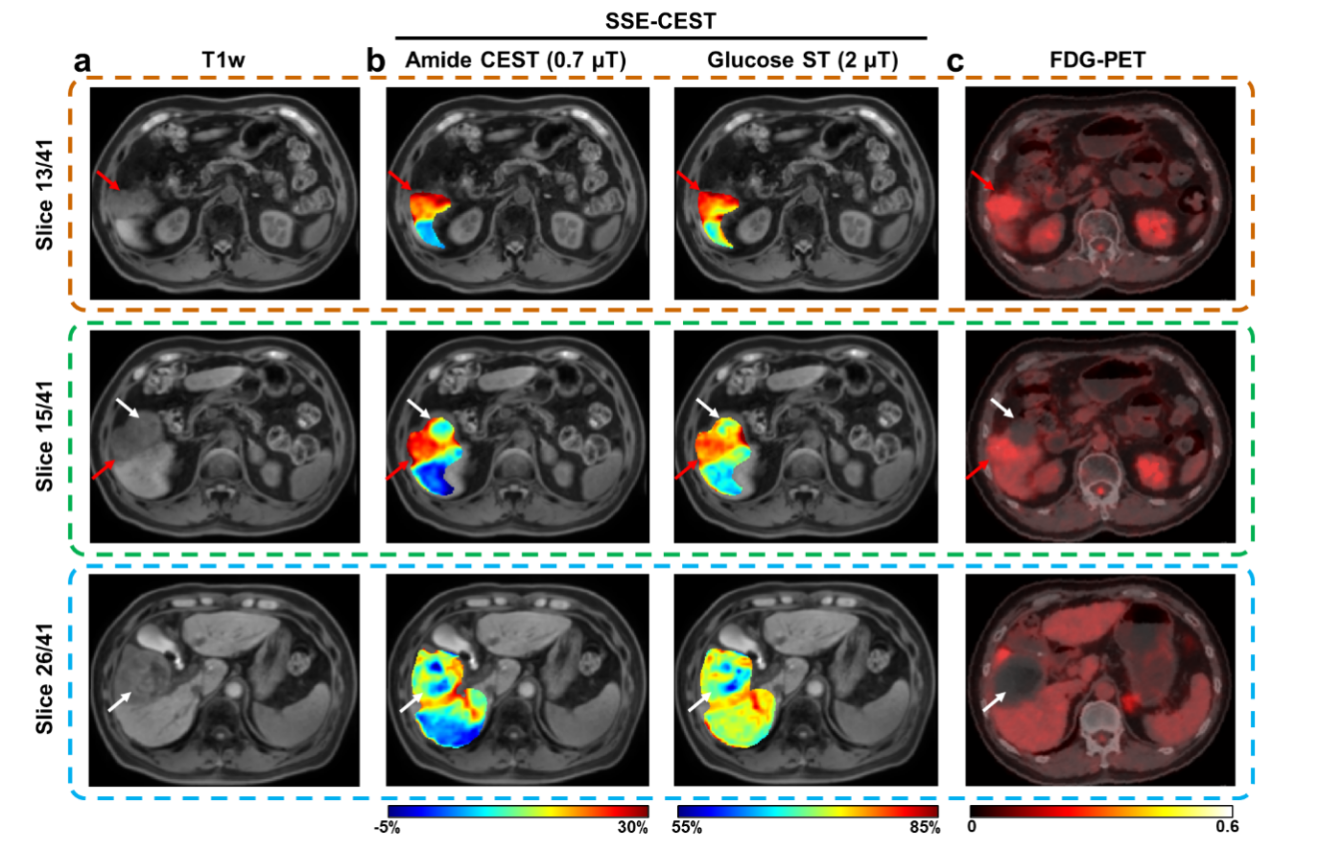

在HCC患者中,活性病灶在0.7 μT的LD图上呈现显著高信号(酰胺CEST、脂肪族NOE、糖原NOE均较坏死组织显著升高,p均<0.01);而坏死灶在所有对比中均为低信号(图6)。APTw(2 μT)未能显示显著差异,提示小B1多池LD分析更具特异性。SSE-CEST代谢图与FDG-PET/CT热区高度匹配,展现出“无标记、无辐射”监测治疗反应的潜力(图7)。

图6 SSE-CEST 技术对肝细胞癌病灶及坏死病灶的三维肝脏代谢图谱分析

图7 一位HCC患者的 SSE-CEST 代谢图与 FDG-PET 图像的对比,该患者在治疗后 10 个月进行扫描